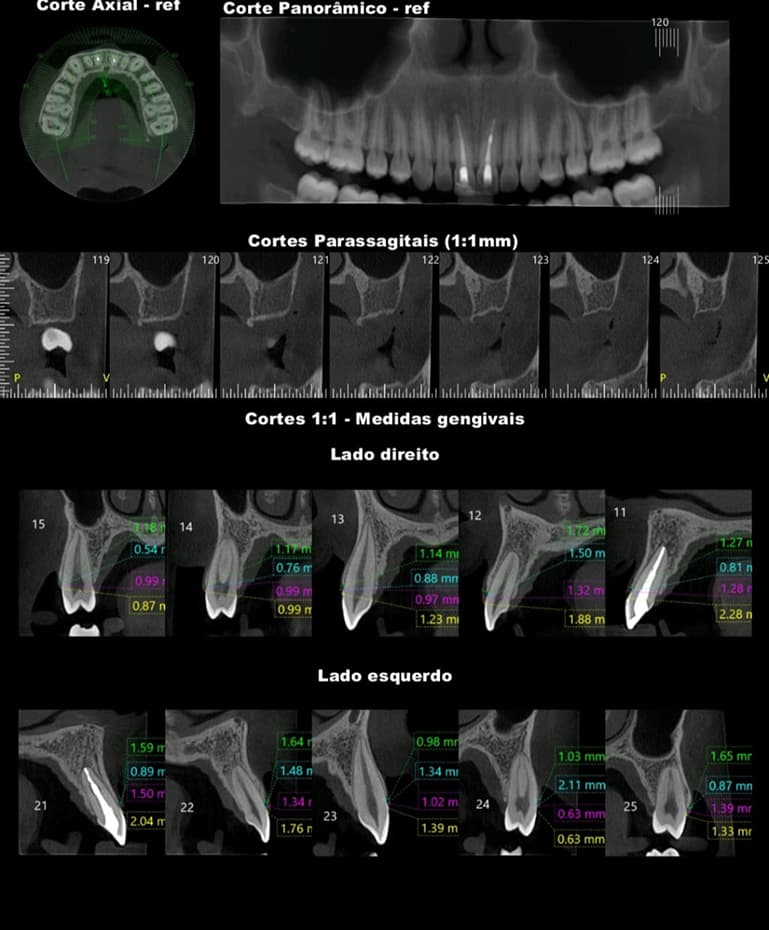

TOMOGRAFIA COMPUTADORIZADA DE ALTA RESOLUÇÃO por feixe Cone Bean - MORITA X800

- MAXILA TOTAL

- MANDÍBULA TOTAL

- REGIÕES: Implantodontia, Periodontia, Cirurgia, Endodontia e Estomatologia